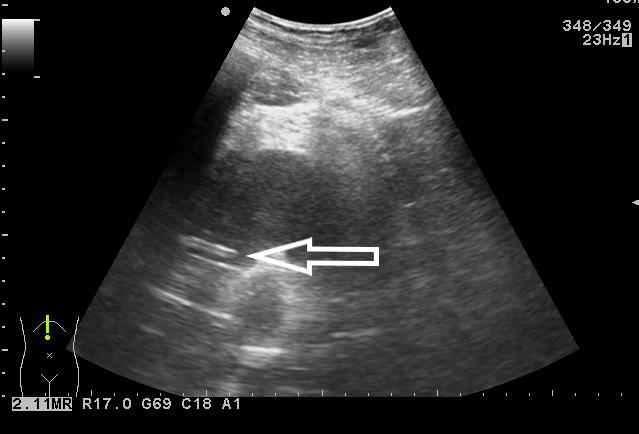

1 资料与方法 1.1 一般资料患者马某某,男,15岁,2019年9月10日以“阑尾切除术后伴腹痛发热6 d”入院。患者8 d前无明显诱因下出现右下腹痛,考虑“急性阑尾炎”,6 d前在当地医院行“阑尾切除术”,术后患者下腹部有持续性疼痛,伴有发热,最高39.3℃,查腹部CT显示:盆腔深部脓肿(图 1),给予抗感染治疗效果不佳,转至蚌埠医学院第一附属医院急诊外科。

| 图 1 下腹部CT显示:盆腔深部脓肿,被肠管,膀胱,骨盆遮挡 |